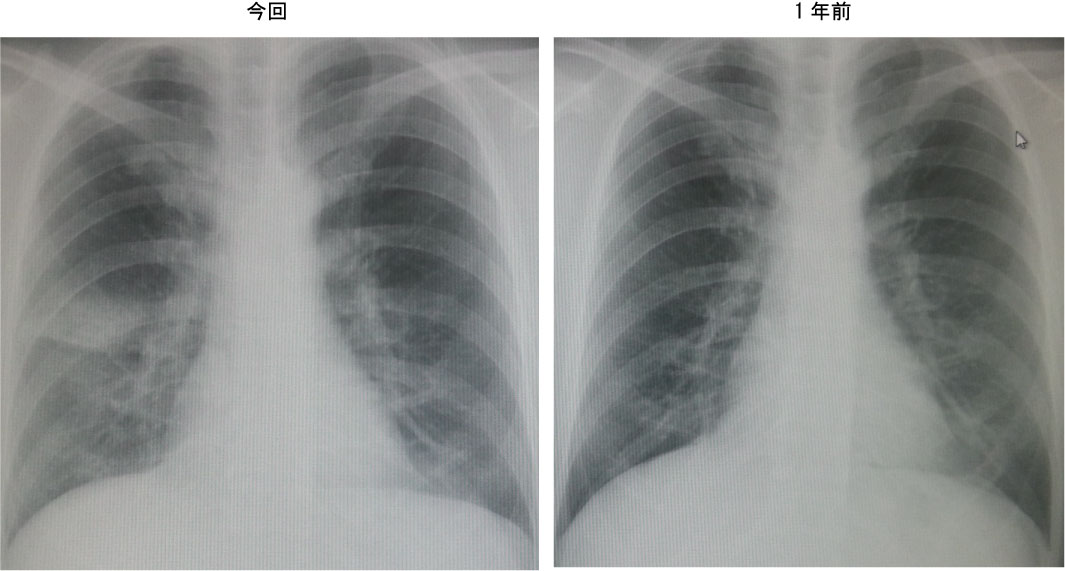

胸部Xp:右肺野限局性浸潤影

胸部CTにてマイコプラズマ肺炎疑い。